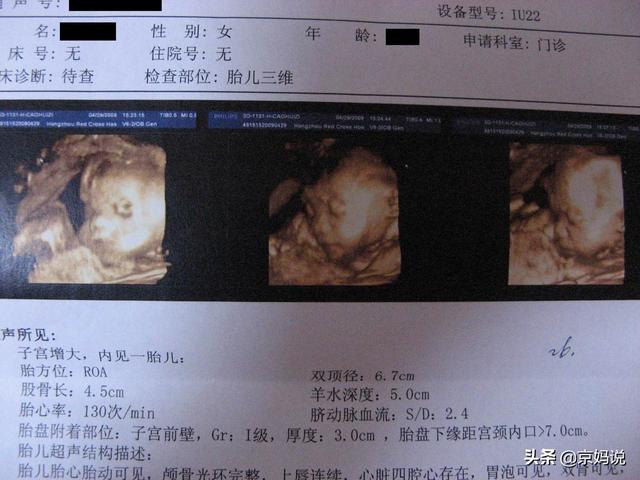

多くの医師たちの回答を読んだが、どの医師も次のようなことには触れていない。妊娠中のママにとって最も重要な超音波検査,結局のところ、妊娠中に行われる超音波検査は4回以上あり、多くの妊婦は超音波検査の指示を受けるときに戸惑う。医師が具体的な説明をしない限り、妊娠中の母親はただ脇に置いておくだけである。

しかし、実際には超音波検査は非常に重要である。 各超音波検査は、体長、体重などの胎児の発育を見ることができるだけでなく、特定の時期に胎児が奇形に罹患する確率を検出することもできる。妊娠中の母親にとって、超音波シートを読めることが重要になる。超音波検査表をもらったら、まずそれを見て、ある指標について理解できなかったり、はっきりしなかったりした場合、あるいは自分の値が正常値から外れていることがわかった場合は、主治医に相談して、その指標が正常であることを確認してください。

妊娠中の超音波検査成績表の見方

超音波検査の成績表を読むには、これらの一般的な検査とその頭字語を理解することが重要です:

両頭頂径(BPD)、後頭前頭径(OFD)、大腿骨長(FL)、上腕骨長(HL)、頭囲(HC)、腹囲(AC)、臍帯血流量比(A/B)、胎児の位置(LOA)、AMN-羊水。

胎児はダイナミックに成長するため、超音波検査ごとに異なるデータが示されます。これらのデータ値は大きすぎるため、ここでは神馬は詳細には触れず、重要なものをピックアップして説明します。